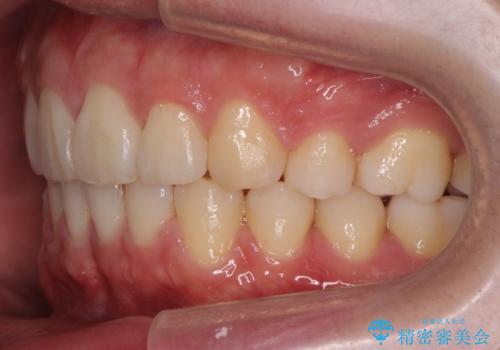

- 出っ歯を主訴に来院。

奥歯の歯ならびのずれが大きく、親知らずを抜いてすべて後ろに下げるか、手前の歯を抜いて前歯を下げるかの2択でした。

時間はかかりましたがしっかり前歯を下げて治療しています。